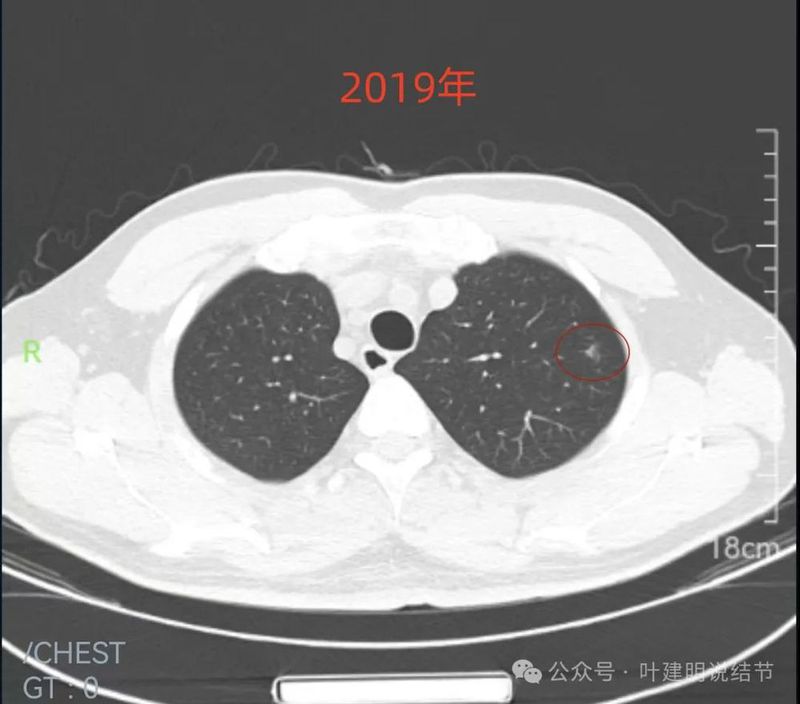

2019年9月时右中叶磨玻璃密度病灶,轮廓与边界清楚,没有实性成分,中间密度稍低,考虑肿瘤范畴的,原位癌或微浸润性腺癌可能性较大。

2019年9月左上叶的磨玻璃结节,轮廓稍显模糊,有血管贴边,膨胀性不足。似乎更符合良性点。